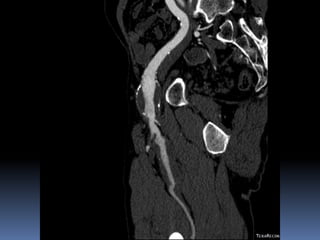

Angioscan: dimensions anévr. ? Angioscan: dimensions Anévr ?

Cas # 1 ♂ 71 ans entrepreneur…  ATCD  PABI ’99  Investigation ‘2011  FCD 35 mm  FPD 30 mm  Popl D 35 mm  Popl G 23 mm  FCG 18 mm

72 59 ATCD: PABI’99 re: AIliaquebil ATCD: Db , ROH Korsakoff, MCASPAC, fempop bilat Anévr popl. Suivi Anévr fém et popl RC: référé rupture…en fait «non» mais symptomatique Quest: … Quest.:C.I. non limitante E.P.: masse puls. > 5cm ing. D non doul et autres… E.P.: masse pulsatile >5 cm ing G doul palpation, nécrose sèche extr dist un orteil non doul Pls périph N Doppler Angioscan: dimensions anévr. ? Angioscan: dimensions Anévr ?

Cas #1 72ans Cas #2 59 ans  Suivi  ATCD  PABI  Particularités  Anévrysme Fémorale profonde  Cutler-Darling type 1  Symptomatique  ATCD  Fem-pop. Bilatéraux…  Particularités  Korsakoff  Cutler-Darling type 2 thrombosés